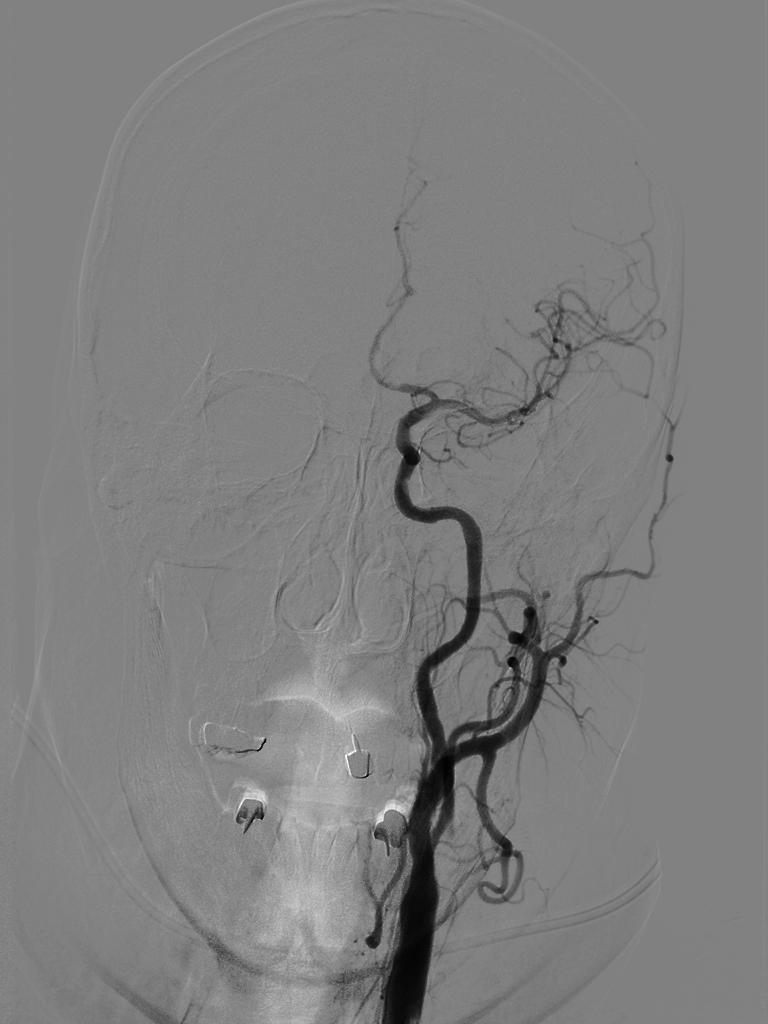

单弯导管辅助长泥鳅导丝置于LC1末端,交换Infinity长鞘至LC1,DSA:LM闭塞。

catalyst 6抽吸导管、Trevo pro-18、Synchro2同轴经长鞘送入,catalyst头端置于LC6,微导丝通过大脑中动脉M1闭塞至M2远端,跟进微导管造影确定血管真腔。